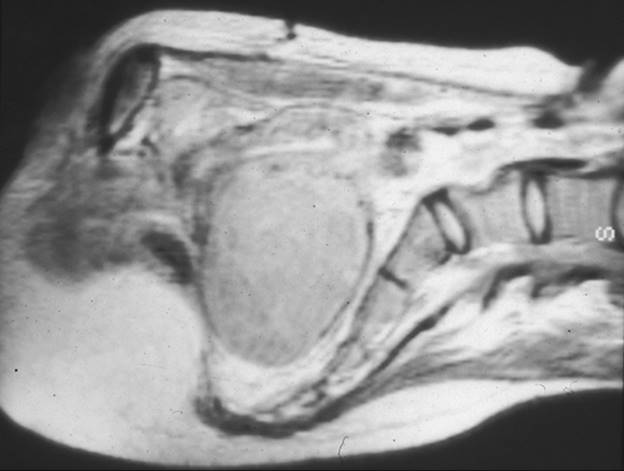

Leiomyomata come to clinical attention for a variety of reasons, and the symptoms (Table 49.1) depend upon tumor size and location (Fig. 49.1). It is unusual but not rare for fibroids to become symptomatic before a woman reaches age 30. Excessive menstrual bleeding (menorrhagia) leading to anemia, debilitating dysmenorrhea, generalized pelvic pain, or symptoms of pressure on the adjacent pelvic viscera my occur, but pain other than dysmenorrhea is typically a late symptom. Vaginal bleeding apart from the expected menses, despite being heavy, is not typically a sign of uterine fibroids and usually indicates an underlying endocrine abnormality such as anovulation. Furthermore, the typical scenario is not a sudden heavy bleeding episode, but rather a gradual increase in menstrual bleeding that parallels the growth of the fibroids. Leiomyomata occasionally undergo rapid enlargement during pregnancy with central avascular necrosis, the so-called red degeneration, resulting in extreme pain requiring hospitalization and narcotics. As the size and number of the leiomyoma increase, particularly with single large subserosal leiomyomata, the adjacent pelvic viscera may become compressed, resulting in urinary frequency, constipation and, occasionally, dyspareunia. Rarely, when the fibroids are large and fill the pelvis or grow laterally from the midportion of the uterine body, they can compress the ureters and cause hydronephrosis (Fig. 49.2). Intracavitary fibroids often are on a vascular pedicle and may be extruded through the cervix, appearing as a necrotic mass. Rarely, large uterine leiomyomata will become entrapped in the pelvis when the expanding tumors are juxtaposed against the promontory of the sacrum and cause the cervix to descend in the vagina and occasionally appear at the introitus. This is particularly true when a woman with large serosal leiomyomata conceives and the tumors, as well as the gravid uterus, enlarge rapidly and can become incarcerated in the pelvis. Although fibroids can be present and cause symptoms at any age after puberty, they typically do not become a clinical problem until the early to mid-30s. With a rising age at which women first attempt pregnancy, this increasingly represents a difficult management problem which did not exist a generation ago when simple hysterectomy was the frequent curative choice. Preserving reproductive potential while relieving symptoms is the challenge today, with the rising age at first pregnancy increasing the likelihood that leiomyomata will develop prior to completing childbearing.

FIG. 49.2. Magnetic resonance imaging of leiomyomata. This magnetic resonance image demonstrates a large leiomyoma arising from the posterior aspect of the uterus and filling the entire pelvis. It directly contacts the promontory of the sacrum.

The vast majority of leiomyomata are detected on pelvic examination performed for routine health maintenance or because of a gynecologic symptom, such as increasing dysmenorrhea, menorrhagia, or pelvic pressure. The uterus typically is enlarged and irregular on bimanual examination. It is important to distinguish leiomyomata from other pelvic masses such as ovarian tumors. This is done most easily with an endovaginal or abdominal ultrasonographic examination, because the leiomyomata appear solid by sonography, with acoustic impedance similar to that of the normal myometrium. Other imaging techniques, such as computerized tomography or magnetic resonance imaging, can prove useful in selected circumstances (see Fig. 49.2, Table 49.3). Indeed, it must be appreciated that detecting an unrelated but clinically important adnexal mass may be difficult when there is a large leiomyoma. Unless the tumor has been stable on pelvic examination for many years in women in the latter reproductive years and beyond, some diagnostic imaging modality is warranted to ensure that the abnormal physical examination findings reflect leiomyomata and not another type of pathology with a greater potential for malignancy. Other imaging modalities, such as computerized tomography or magnetic resonance imaging, can distinguish leiomyomata from adnexal pathology, but they are much more expensive and time consuming and yield no more useful information than simple office sonography.